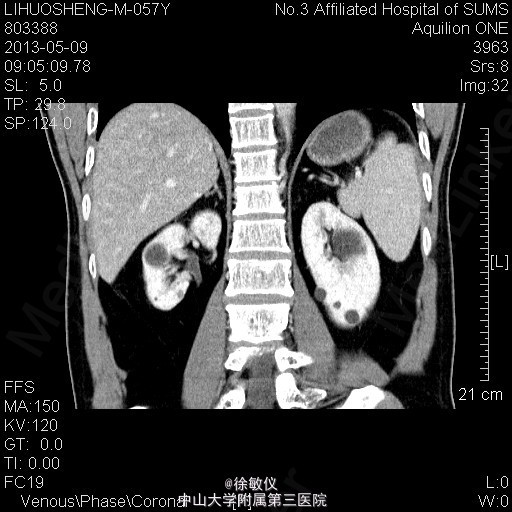

看图片,你的诊断是什么?

老年男性,发现血压升高1年余。平素有降压治疗,但血压控制欠佳,血压最高210/110mmHg,平时血压波动在160-190/90-110mmHg。